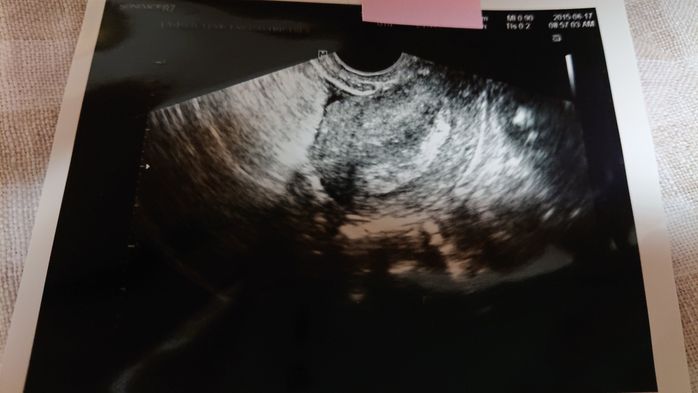

《妊娠5週目のエコー写真》

初めてのエコー検査からちょうど1週間後、赤ちゃんがおなかにやってきてくれたか、再度、確認する日がやってきました。まだ、赤ちゃんの姿は見えないけれど、胎嚢という赤ちゃんが育つためのお部屋が出来ているのを確認できました。胎嚢はエコー写真の黒丸部分です。私自身、「自分の体は妊娠できるのか」と長年不安だったので、前回は何も写っていなかったエコー写真を見たときは不安でしたが、今回は、くっきりと赤ちゃんのお部屋である胎嚢を見つけることができ、感動しました。